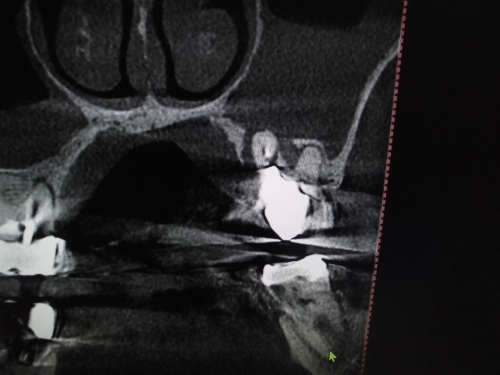

上顎洞との位置関係が確認できます。

CTでは近心の第二根管も確認できます。